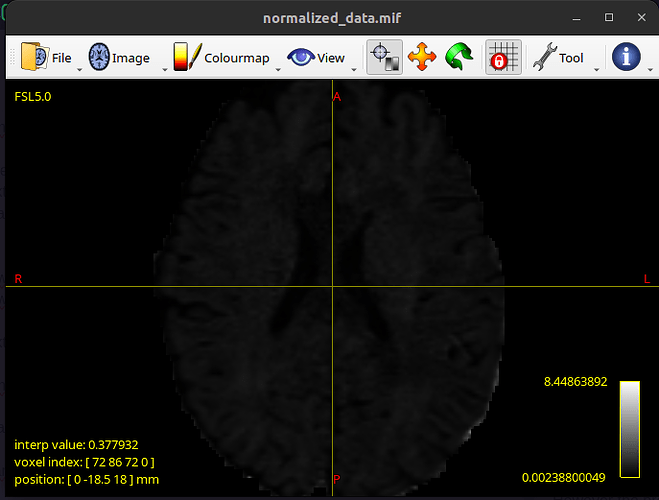

However the problem is with the normalized data. It looks like the following: